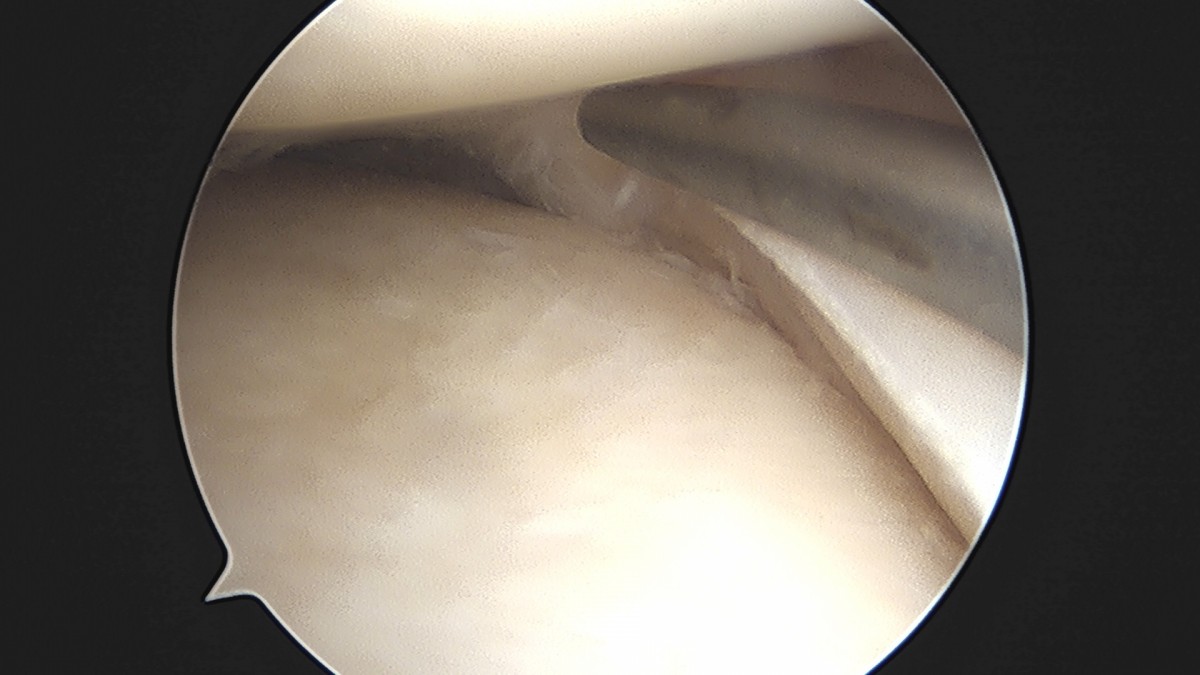

이재상원장님 무릎 반월상 연골판 절제술 고기O 환자

dae765e4d9ac96aee867c9d6292d8784_1758005092_2595.jpg